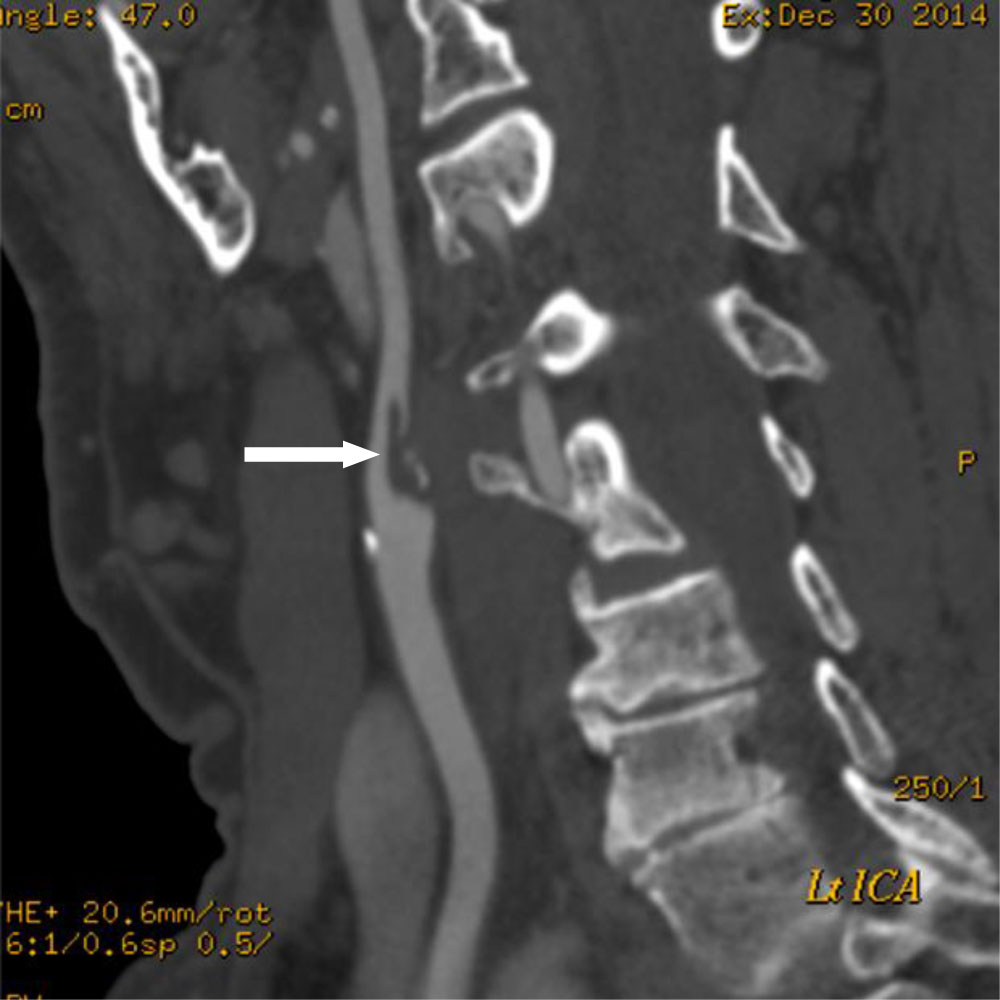

CT Angiography demonstrated a large ruptured plaque of heterogeneous morphology in the Left ICA associated with a propagating Thrombus (Figure 3). These findings were associated with a dominant Left PCOM feeding the Left Posterior Cerebral circulation and thereby explaining the fact that the plaque present in the Left ICA was able to seed the Left Middle Cerebral and the Left Posterior Cerebral circulation and in fact; the origin of the multi-territory Stroke as demonstrated on the MRI scan was not Cardio-Embolic but in fact related to his underlying Carotid disease. The patient underwent a successful Left Carotid Endarterectomy and has made an excellent functional recovery. He remains on high dose Statin and Anti-Platelet therapy. The decision to investigate the presumed moderate Carotid Stenosis demonstrated on Duplex imaging with CT Angiography was central to the diagnosis and further management.

Figure 3: CT Carotid Angiography demonstrating a large ruptured plaque in the Left Internal Carotid Artery (white arrow). View Figure 3